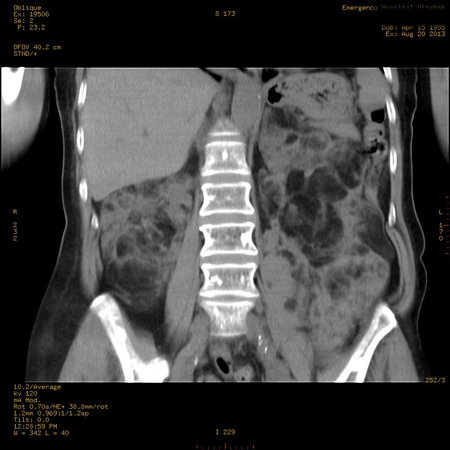

УЗИ почек - туберозный склероз

Пожилая женщина с нормальными мочевиной и креатинином.

Ангиомиолипоматоз почек , думаю компонент туберозного склероза.

Да, туберозный склероз.

Случай консультирован на кафедре радиологии Католического университета г.Лёвен (Бельгия) - зав каф. профессор Р.Оуен.